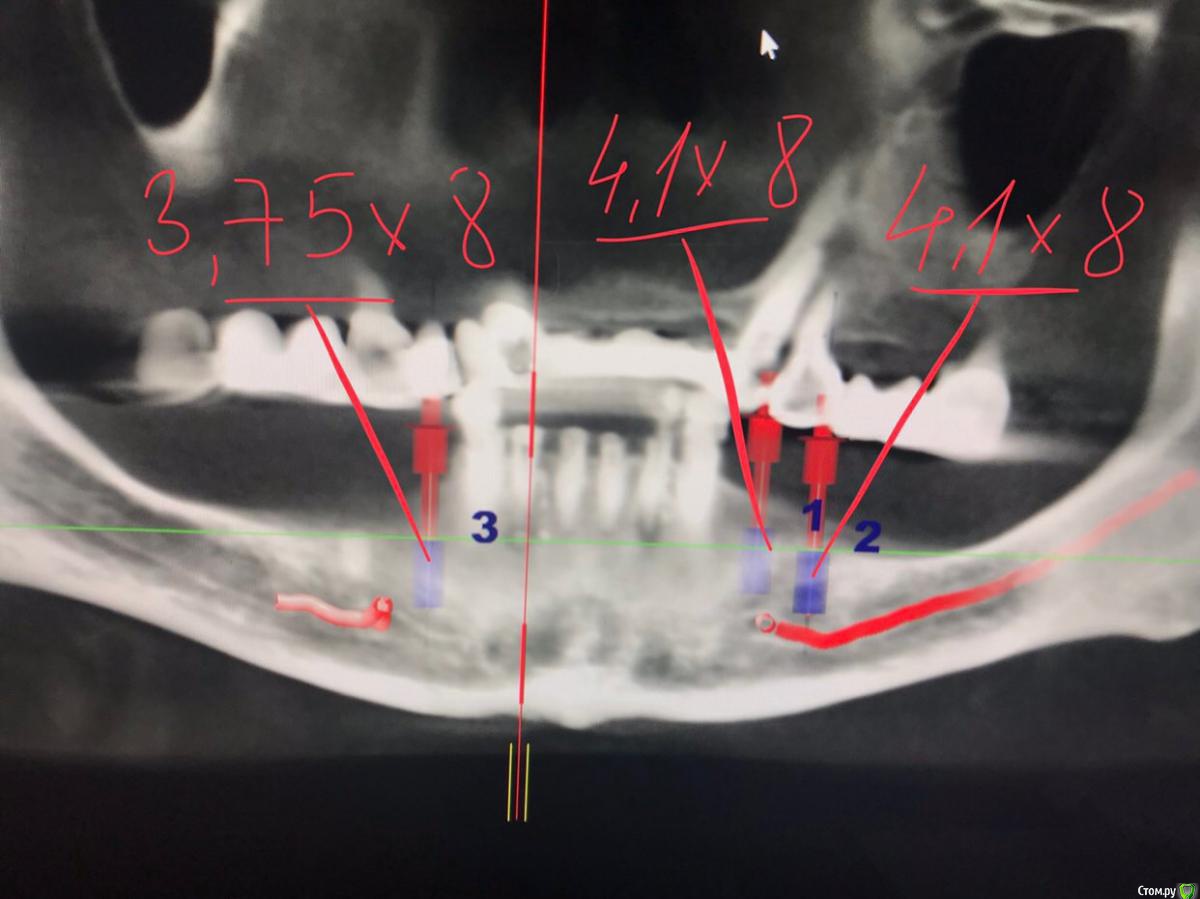

dr.Dre Опубликовано 27 мая, 2018 Поделиться Опубликовано 27 мая, 2018 Добрый вечер уважаемые коллеги ,посмотрите правильно ли расставлены мплантанты , пациентка 60 лет от 33 до 43 все будет удаляться, планирую поставить балку незнаю где поставить 4 импл.?Второй клинический случай можна ли поставить 12 мм имплант,а вестибулярную стенку засыпать графтом? Ссылка на комментарий

Nazim_NV86 Опубликовано 27 мая, 2018 Поделиться Опубликовано 27 мая, 2018 Добрый вечер. 1. Глубоко. 2. 44 прямо на склон, будут проблемы с позиционированием. 3. НКР всё равно делать надо, либо отогнуть вестибулярку с нижним горизонтальным пропилом. Удаляйте, разглаживайте всё, и по ходу дела увидите оптимальные позиции. 43 - 34 нормально. Ссылка на комментарий

Evikrol Опубликовано 27 мая, 2018 Поделиться Опубликовано 27 мая, 2018 (изменено) Если хотите балку, можно смело ставить в лунки клыков и резцов, только я бы редукцию небольшую сделал костными кусачками, хотя бы на 5 мм, чтобы балка поместилась. Длинна 11,5 или 13 мм. Только внимательно изучите кт и запомните направление сверления, что бы не перфорировать вестибулярную стенку Лучше конечно всена4, но надо уметь работать с мультиюнитами Изменено 27 мая, 2018 пользователем Evikrol Ссылка на комментарий

АнтонТЛТ Опубликовано 27 мая, 2018 Поделиться Опубликовано 27 мая, 2018 Ставить в позиции 4-2-2-4 с редукцией кости. Под балку параллельно, под all-on-4 с наклоном четверок под угловые мультиюниты вашей системы. 1 Ссылка на комментарий